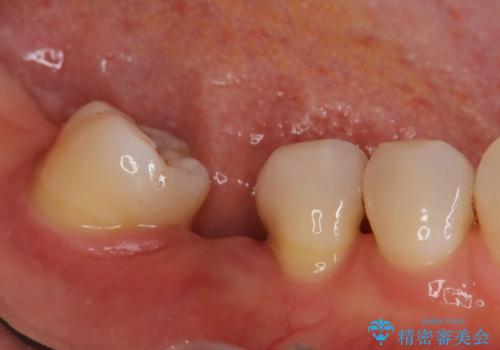

右下7番の部分矯正: 次に、傾いていた7番を垂直に起こすための部分矯正を実施しました。これにより、6番に入れるインプラントのためのスペースが確保され、咬み合わせの軸が安定しました。